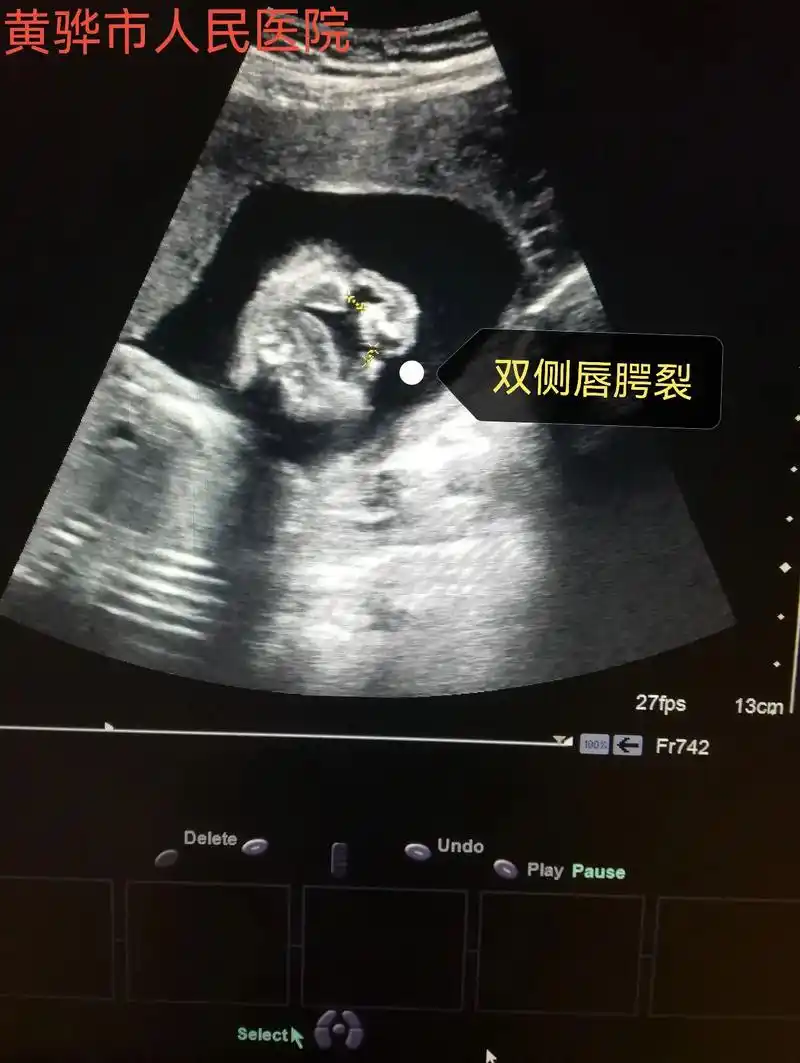

胎儿专场,24周四维胎儿唇腭裂,其他暂时未发现异常,需要评估 - 抖音